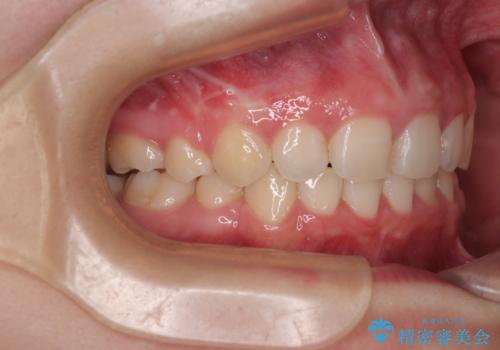

飛び出した前歯はしっかりと引っ込み、横顔の印象が大きく変化しました。

- 下唇の上に乗っかってしまうくらい前歯が飛び出していることを気にして来院された患者様です。

唇を閉じようとするとオトガイ部に力が入ってしまい、うまく閉じることができない状態であったため、上下左右の第一小臼歯4本を抜歯して、ワイヤー装置にて矯正治療を行うこととしました。